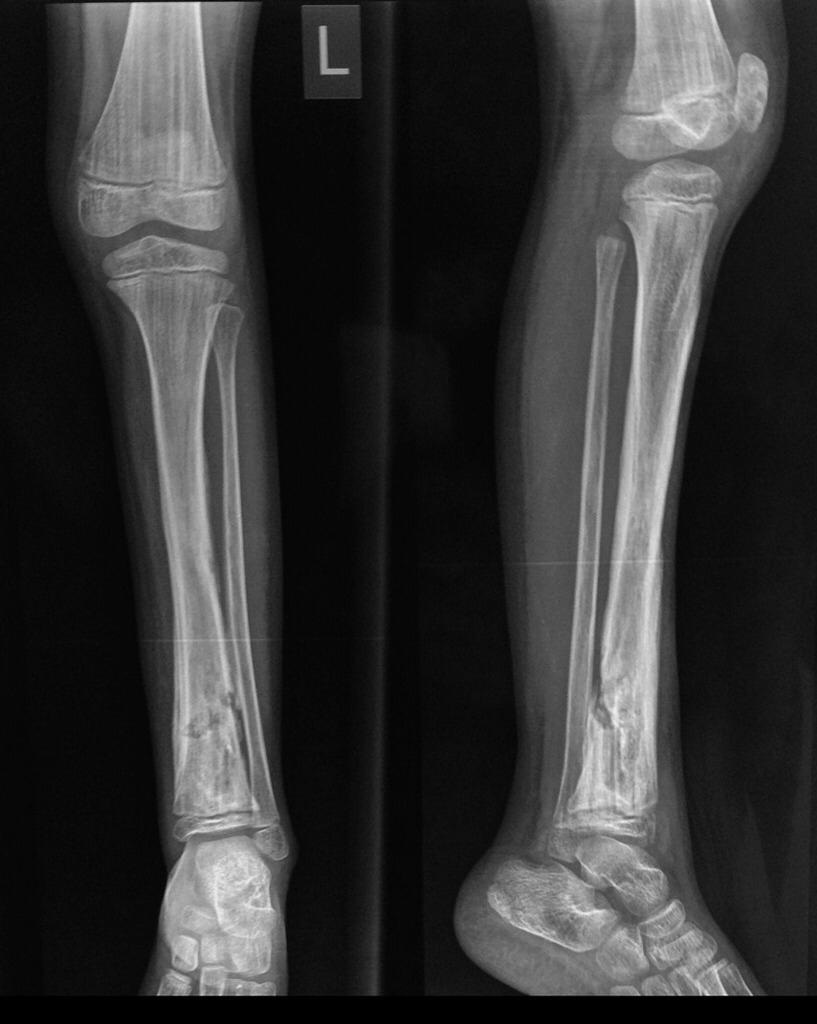

Radiografía Simple

La radiografía simple sigue siendo la técnica diagnostica inicial ante la sospecha de osteomielitis. La Osteomielitis crónica: se caracteriza por necrosis ósea con destrucción trabecular y formación de abscesos intraóseos que pueden contener secuestros (fragmentos de...